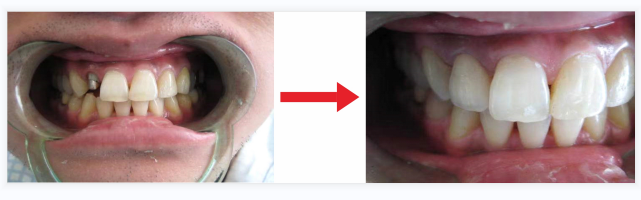

三.樁核冠修複技(jì )術(殘冠修複技(jì )術)

樁核冠是修複大面積牙體(tǐ)缺損的一種常用(yòng)的修複方法。由于剩餘的牙體(tǐ)組織量少,無法單獨使用(yòng)全冠獲得良好固位。為(wèi)了增加固位,将修複體(tǐ)的一部分(fēn)插入根管内獲得固位,插入根管内的這部分(fēn)修複體(tǐ)稱為(wèi)樁,上部制作(zuò)稱為(wèi)牙冠。

适用(yòng)範圍:殘根、殘冠等大面積牙體(tǐ)缺損。